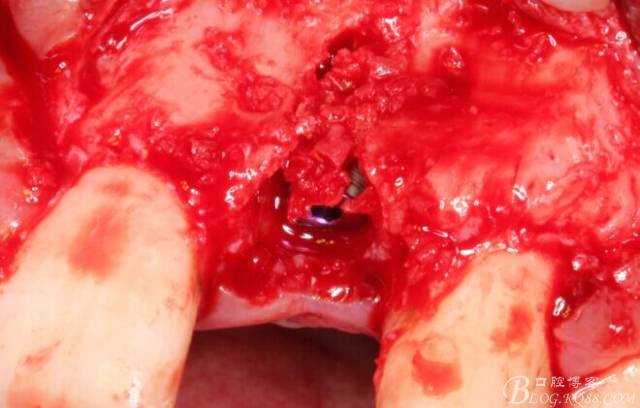

于是我果斷告知患者,手術(shù)失敗了,不能拖延,如不及時(shí)處理,炎癥繼續(xù)發(fā)展會(huì)很快波及鄰牙牙槽骨?;颊呓邮芪业慕ㄗh。切開(kāi)翻瓣,骨粉及生物膜消失了,骨吸收嚴(yán)重,幸運(yùn)的是,因?yàn)樘幚砑皶r(shí),鄰牙骨支持依然存在。

徹底掻刮。